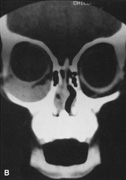

Magnetic resonance imaging is useful in selected cases, especially when evaluating the orbital cranial junction. Significant bony artifact and a lack of orbital fat in the orbital apex make CT scan resolution of the orbital apex structures poor. Because cortical bone has low signal on MRI, there is no bone artifact when viewing the orbital apex on MRI. The lack of intervening fat in the apex to provide contrast is overcome on MRI because contrast is provided by the individual nuclear characteristics of each tissue so that the orbital apex structures are visualized well. Consequently, conditions that affect the optic nerve and chiasm, such as optic nerve meningioma and glioma, generally are evaluated with MRI rather than CT scan (Fig. 2).

Fig. 2. A. Axial orbital CT scan of right optic nerve meningioma. Note lack of detail in orbital apex. B. Axial orbital MR image, same patient. Note increased detail in orbital apex owing to lack of bone artifact. C. MRI with gadolinium contrast. Note extension into brain not easily appreciated with CT scanning or MRI without contrast.